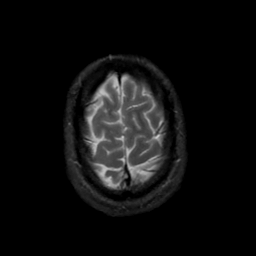

MR Study #20 October 6, 1991 -- Slice #44

[Home][Help][Clinical][Tour 1][Tour 2] Slice 44